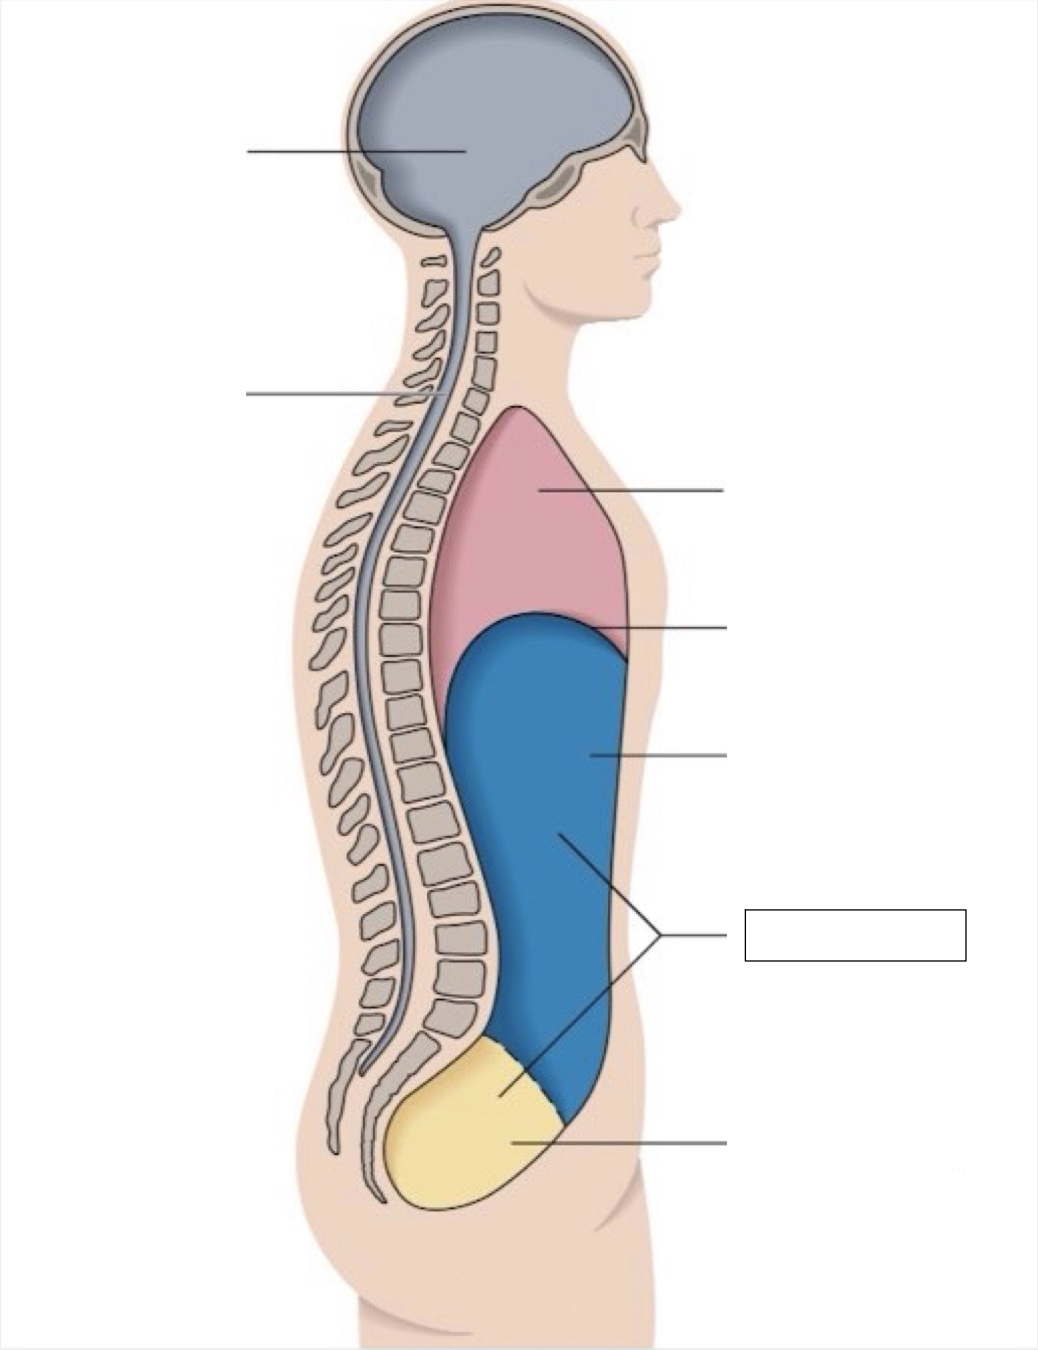

thoracic cavity

diaphragm

abdominal cavity

abdomino-pelvic cavity

pelvic cavity

spinal cavity

cranial cavity